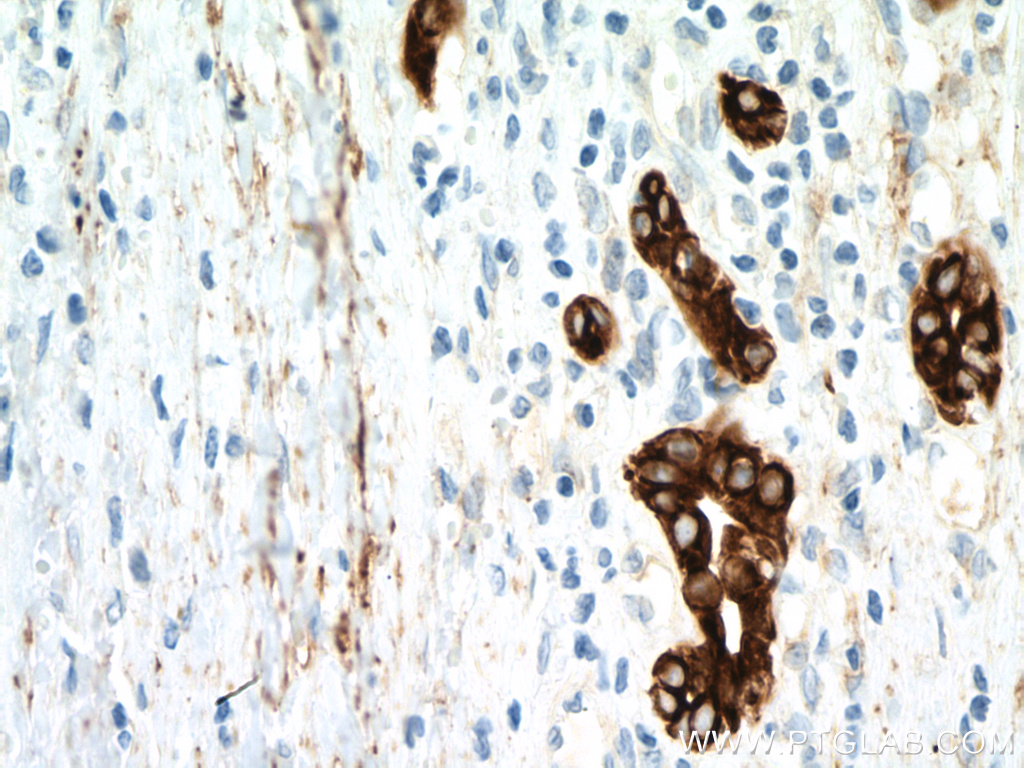

IHC staining of human breast cancer using 66187-1-Ig (same clone as 66187-1-PBS)

Immunohistochemical analysis of paraffin-embedded human breast cancer tissue slide using 66187-1-Ig (Cytokeratin 18 antibody) at dilution of 1:2400 (under 40x lens). Heat mediated antigen retrieval with Tris-EDTA buffer (pH 9.0). This data was developed using the same antibody clone with 66187-1-PBS in a different storage buffer formulation.